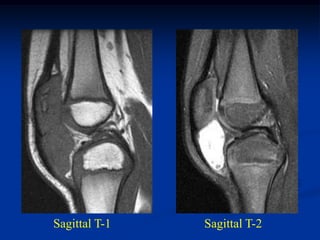

CLASSIC     Case #285         Sagittal T-1 MRI

67 year female with myxoid liposarcoma knee

Sagittal T-2 MRI

Axial T-2 MRI

CLASSIC Case #285 Sagittal T-1 MRI 67 year female with myxoid liposarcoma knee